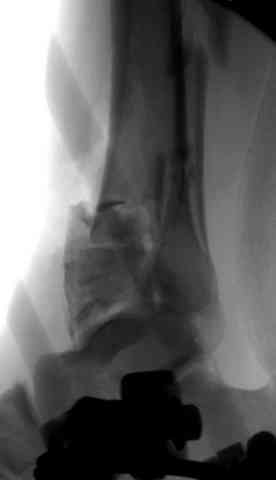

2. Второе. Следует обязательно усилить фиксацию: спицы через передний отдел стопы и пяточную кость, вторая спица через проксимальное кольцо и 1-2 стержня в проксимальный отломок б/б кости. Сроки фиксации до 8 недель. Аппаратом можно устранить, кажется, появившийся вальгус. В подобных ситуациях лучше ведут себя стержни, которыми можно сопоставить и сдавить лодыжки и задний край б/б кости. Привожу случай восстановления голеностопного сустава спустя 2,5 мес.(этап лечения) после травмы со стержнями.

3. Дистальную опору можно было бы взять в виде ¾ кольца или двух разноуровневых полуколец, соединенных небольшими стяжными стержнями. ¾ кольца - не давят на стопу, а разноуровневые полукольца «обходят» сустав. Одно снизу, другое сверху.